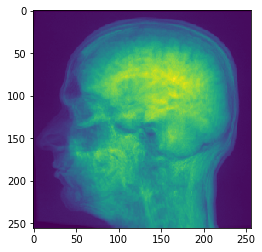

# Maximum Z Projection

projection = cle.maximum_z_projection(input_image)

# show result

cle.imshow(projection)

../_images/d8f11fbbae3f5e1e60dde436a78650ecc23e15279f1765bc78de1dc6c6bfe485.png

如果你将图像堆栈传递给cle.imshow,它会为你沿Z轴进行最大强度投影:

cle.imshow(input_image)